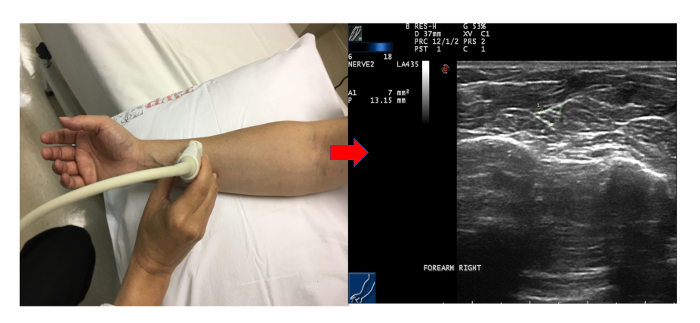

Tambien puede realizarse ecografía de partes blandas, preferiblemente con ecografía de alta resolución.

Tunel Carpo eco